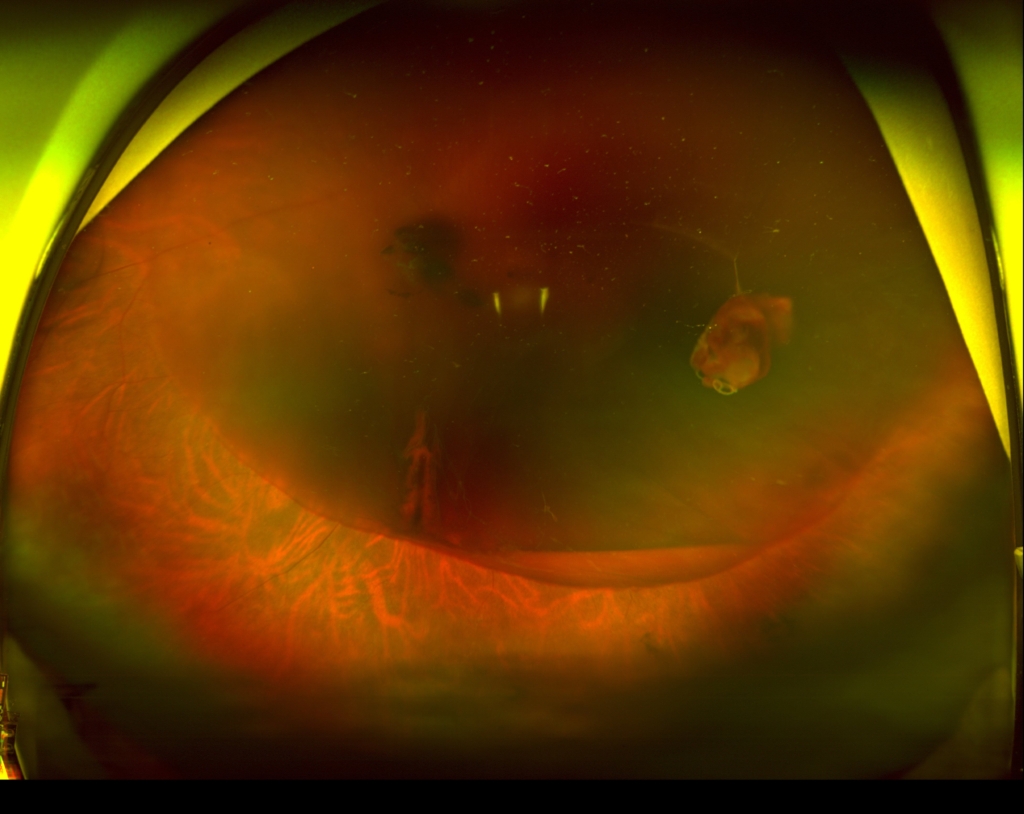

耳側下方弁状裂孔による網膜剥離

60歳 女性主訴 3週間ほど前から飛蚊症、1週間前から視力低下を自覚視力 左眼 0.09(n.c) 硝子体手術(経毛様体扁平部硝子体切除 Pars Plana Vitrectomy:PPV、眼内レーザー、20%SF6ガス置換)+水晶体再建術を行った。 3時から8時に黄斑剥離を伴う胞状...